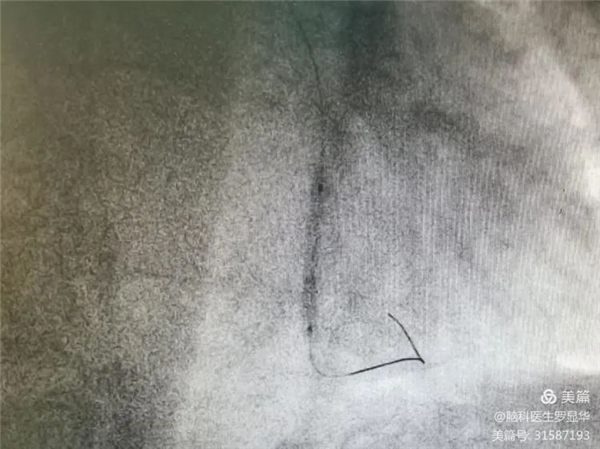

釋放冠脈球擴(kuò)支架